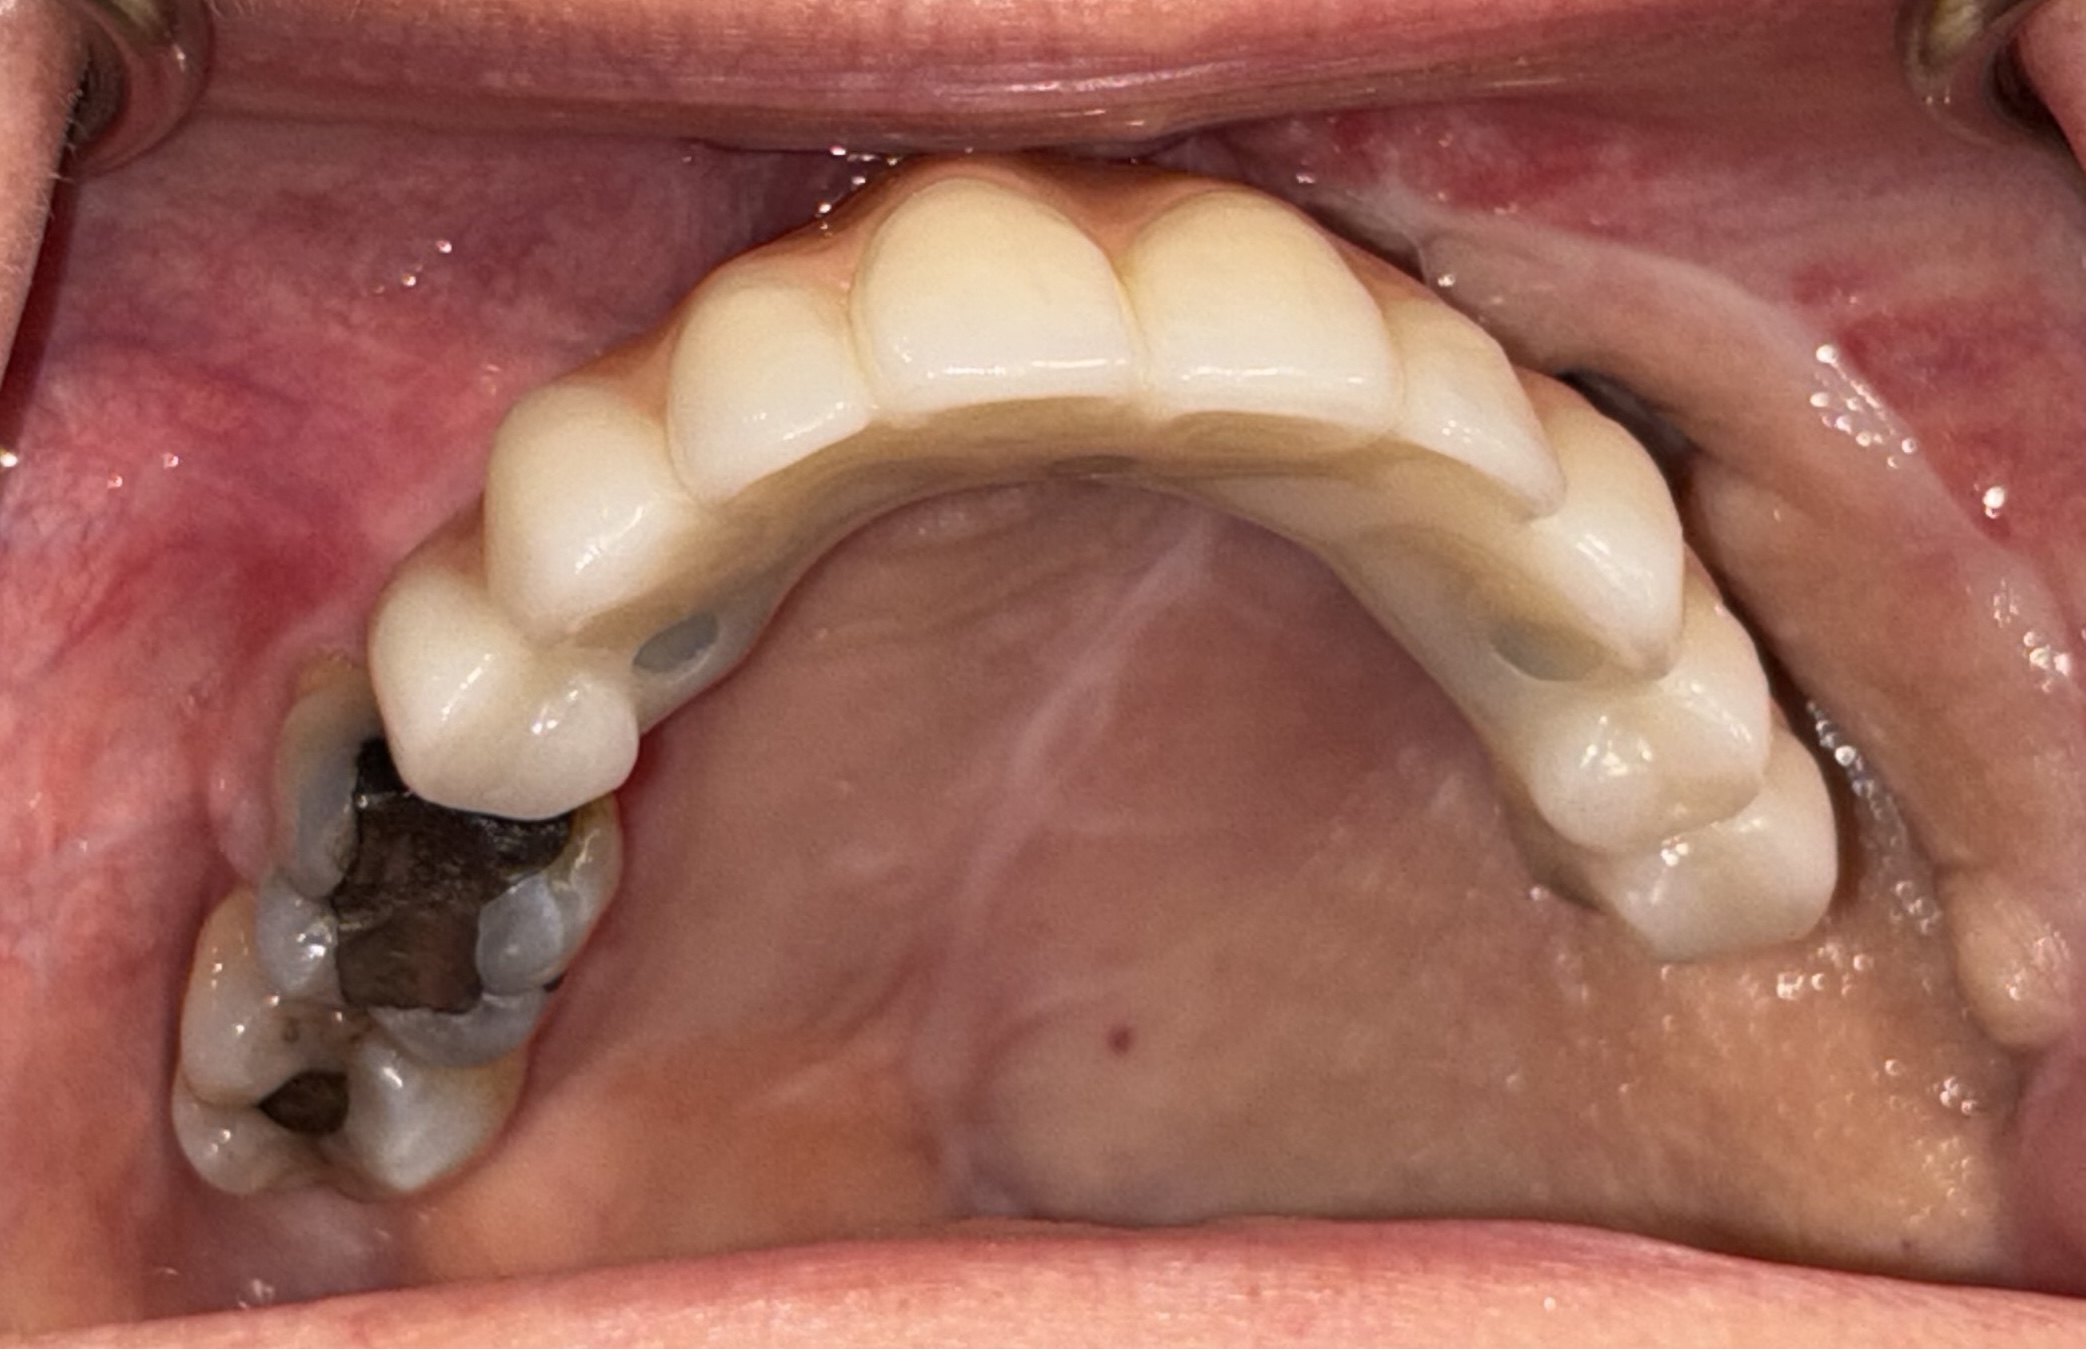

Fixed zygomatic implant-retained prosthesis following ZIP-Flap reconstruction

The Zygomatic Implant Perforated (ZIP) Flap combines free flap reconstruction with simultaneous intraoperative zygomatic implant placement — enabling fixed dental rehabilitation within weeks of ablative surgery for low-level maxillary malignancy.

First described in 2017 and supported by a prospective cohort of 35 consecutive cases, the ZIP Flap is rapidly becoming international standard of care. A dedicated training programme operates annually at Keele Medical School.

Implant outcome — Wirral Implants, Heswall Dental Practice